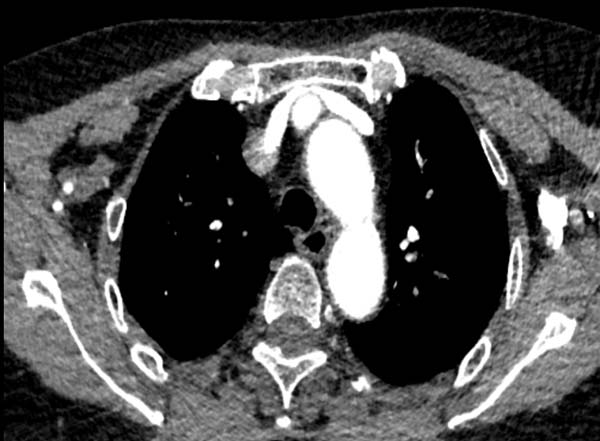

左侧锁骨下静脉需跨过主动脉弓,路程较远且比较迂曲,受解剖结构影响,左侧锁骨下静脉狭窄较右侧更为多见,且一般狭窄程度重于右侧,注射对比剂时遇到阻力较大,容易出现以下情况:

1) 由于受主动脉压迫导致对比剂冲入浅表静脉网中,受阻严重导致团注效果不佳。

头臂干压迫左头臂静脉

左侧锁骨下静脉受主动脉弓挤压,

导致对比剂冲入浅表静脉网中

左侧锁骨下静脉受主动脉弓挤压 血管充盈不佳

2) 左上肢留置针穿刺高速团注对比剂时,不但行程远、还受主动脉弓压迫导致进入右心房的时间延长,同等体重患者需增加注射压力和药量。